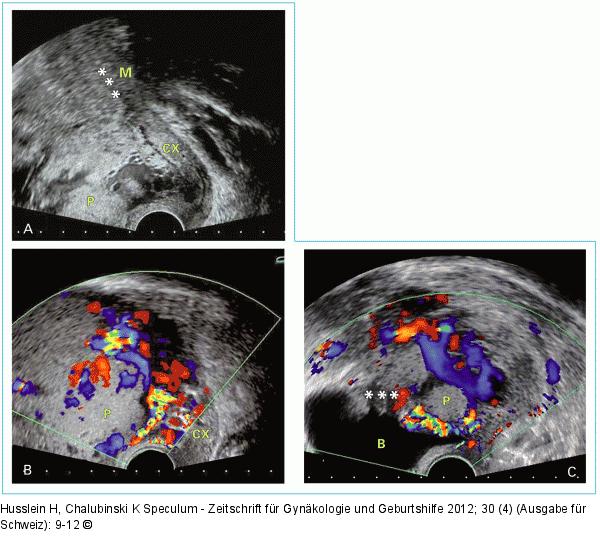

Abbildung 1a-c: Placenta praevia percreta Placenta praevia percreta. (A) B-Bild – Grenzverlust Plazenta/Myometrium; (B) Hypervaskularisation und Gefäßlakunen; (C) retrovesikale Serosa, gefäßdurchsetzt. P: Plazenta; CX: Zervix, B: Blase; M: Myometrium; ***: Grenzverlust |

Placenta praevia percreta. (A) B-Bild – Grenzverlust Plazenta/Myometrium; (B) Hypervaskularisation und Gefäßlakunen; (C) retrovesikale Serosa, gefäßdurchsetzt. P: Plazenta; CX: Zervix, B: Blase; M: Myometrium; ***: Grenzverlust |